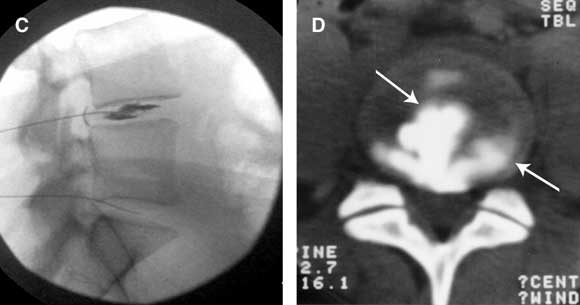

Provocation discography (Figure C) To test if a particular intervertebral disc is painful, contrast medium is injected into the disc to distend it. The disc is deemed to be the source of pain if the patient’s accustomed pain is reproduced at low pressure of injection, provided that stimulation of adjacent discs does not reproduce pain. Computed tomography discography (Figure D) After a discogram has been performed, the internal architecture of the disc can be demonstrated by computed tomography (CT). Radial fissures correlate strongly with the disc being painful. |

![]() C: Lateral radiograph of an L4–L5 discogram, showing needles placed in the L4–L5 and L5–S1 intervertebral discs and contrast medium injected into the L4–L5 disc. D: Post-discography CT scan of (a painful) L4–L5 intervertebral disc. Contrast medium outlines a radial and a circumferential fissure (arrows), diagnostic of internal disc disruption. |